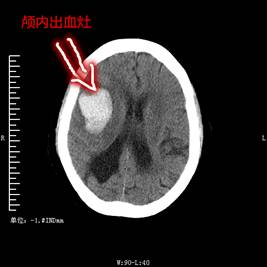

明,母亲是整个家庭的凝聚力,作为儿女不愿失去一生辛苦的母亲,强烈要求全力救治但又因经济原因,治疗经费困难而担心医院是否及时救治。科室讨论后立即上报了医院领导和相关科室后指示先全力救治并制定了切实可行的治疗方案。马尔康当地政府部门和当地村民也积极帮扶并发动水滴筹来为陈阿姨筹集救治经费。在治疗经费欠缺的但患者病情危急的紧急关头,神经外科黎明主任及主治医师文家智、向庆勇,罗俊毅医师,重症医学科张泽奎主任、胡林虎医师集体会诊后确认清除颅内血肿对陈阿姨预后恢复自理能力有帮助,积极建议给陈阿姨进行开颅血肿清除。经过医患双方充分准备后,陈阿姨在2018年06月28日在全麻下进行了“右侧额叶开颅血肿清除术”。